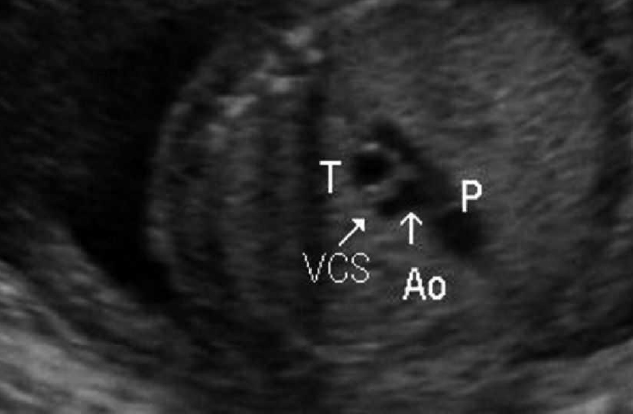

Las obstrucciones de la vía área incluyen la atresia u obstrucción de la laringe, tráquea o bronquial. La atresia laríngea o traqueal es una obstrucción o falta de formación de la vía aérea fetal al nivel de la laringe o la tráquea que ocasiona un crecimiento excesivo de ambos pulmones debido a la acumulación de los fluidos pulmonares en su interior.

Por otro lado, la atresia bronquial es una obstrucción ó falta de formación de la vía aérea fetal a nivel bronquial que ocasiona un crecimiento excesivo del pulmón afectado debido a la acumulación de los fluidos pulmonares en su interior.